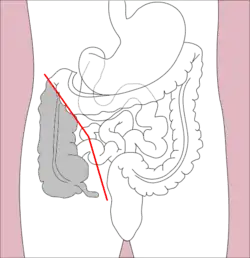

Right hemicolectomy and left hemicolectomy refer to the resection of the ascending colon (right) and the descending colon (left), respectively. When middle colic vessels and transverse colon are also resected, it may be referred to as an extended hemicolectomy.[20] Left hemicolectomy is most commonly indicated for cancer in the splenic flexure or descending colon, diverticular disease of the descending colon, and colovesicular or colovaginal fistulas that develop as a consequence of diverticular disease.[11] The main limitation to performing a left extended colectomy is the difficulty of achieving a colorectal anastomosis afterward. Different techniques, such as Deloyer's or Rosi-Cahil's techniques, have been proposed to solve this issue.[21] Right hemicolectomy is most commonly indicated for masses in the right, or ascending, colon but may also be performed for neoplasms of the cecum or appendix. Right-sided diverticulitis, cecal volvulus, inflammatory bowel disease, and adenomatous polyps are benign conditions that may require right hemicolectomy.[11]